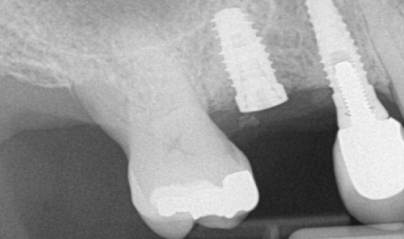

Η διαδικασία αυτή απαιτεί συνεργασία ανάμεσα στον περιοδοντολόγο και τον οδοντίατρο που θα κάνει την αποκατάσταση του εμφυτεύματος (θήκη, γεφυρα, οδοντοστοιχία). Μετά από επικοινωνία με τον οδοντίατρο και την ανάλυση τρισδιάστατης ακτινογραφίας αποφασίζεται η ακριβής θέση του εμφυτεύματος. Στη συνέχεια κατασκευάζεται χειρουργικός νάρθηκας ο οποίος χρησιμοποιείται ως οδηγός κατά την τοποθέτηση του εμφυτεύματος.

Είναι η τοποθέτηση εμφυτευμάτων με τη βοήθεια ηλεκτρονικού υπολογιστή η οποία προσφέρει μέγιστη ακρίβεια και προβλεψιμότητα στην τοποθέτηση του εμφυτεύματος. Μετά τη λήψη τρισδιάστατης ακτινογραφίας, το περιστατικό σχεδιάζεται με τη βοήθεια ηλεκτρονικού υπολογιστή όπου επιλέγεται η ιδανική θέση του εμφυτεύματος. Με βάση τη θέση αυτή κατασκευάζεται χειρουργικός νάρθηκας ο οποίος εφαρμόζει στα γειτονικά δόντια την ώρα της επέμβασης και καθοδηγεί την τοποθέτηση του εμφυτεύματος ώστε να γίνεται με μεγάλη ακρίβεια. Με τον τρόπο αυτό, σε αρκετές περιπτώσεις μειώνεται η ανάγκη για οστικό μόσχευμα πριν ή κατά την τοποθέτηση του εμφυτεύματος και συνεπώς η ταλαιπωρία του ασθενούς